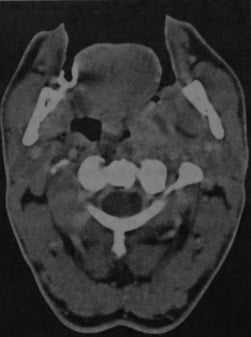

КТ с контрастированием: левосторонний паратонзиллярный абсцесс. Образование имеет гипоинтенсивный центр, окруженный усиленной стенкой. Отек левой нёбной миндалины и слизистой глотки на стороне поражения вызывает асимметричное сужение глотки. Рот остается открытым в связи с болевым синдромом.

КТ с контрастированием (реконструкция во фронтальной плоскости): левосторонний паратонзиллярный абсцесс. Выявляется перифокальный отек и повышенная плотность слизистой, а также асимметричное сужение ротоглотки, распространяющееся в дистальном направлении слева от мягкого нёба. В абсцессе наблюдается типичное периферическое усиление с гипоинтенсивной полостью в центре.